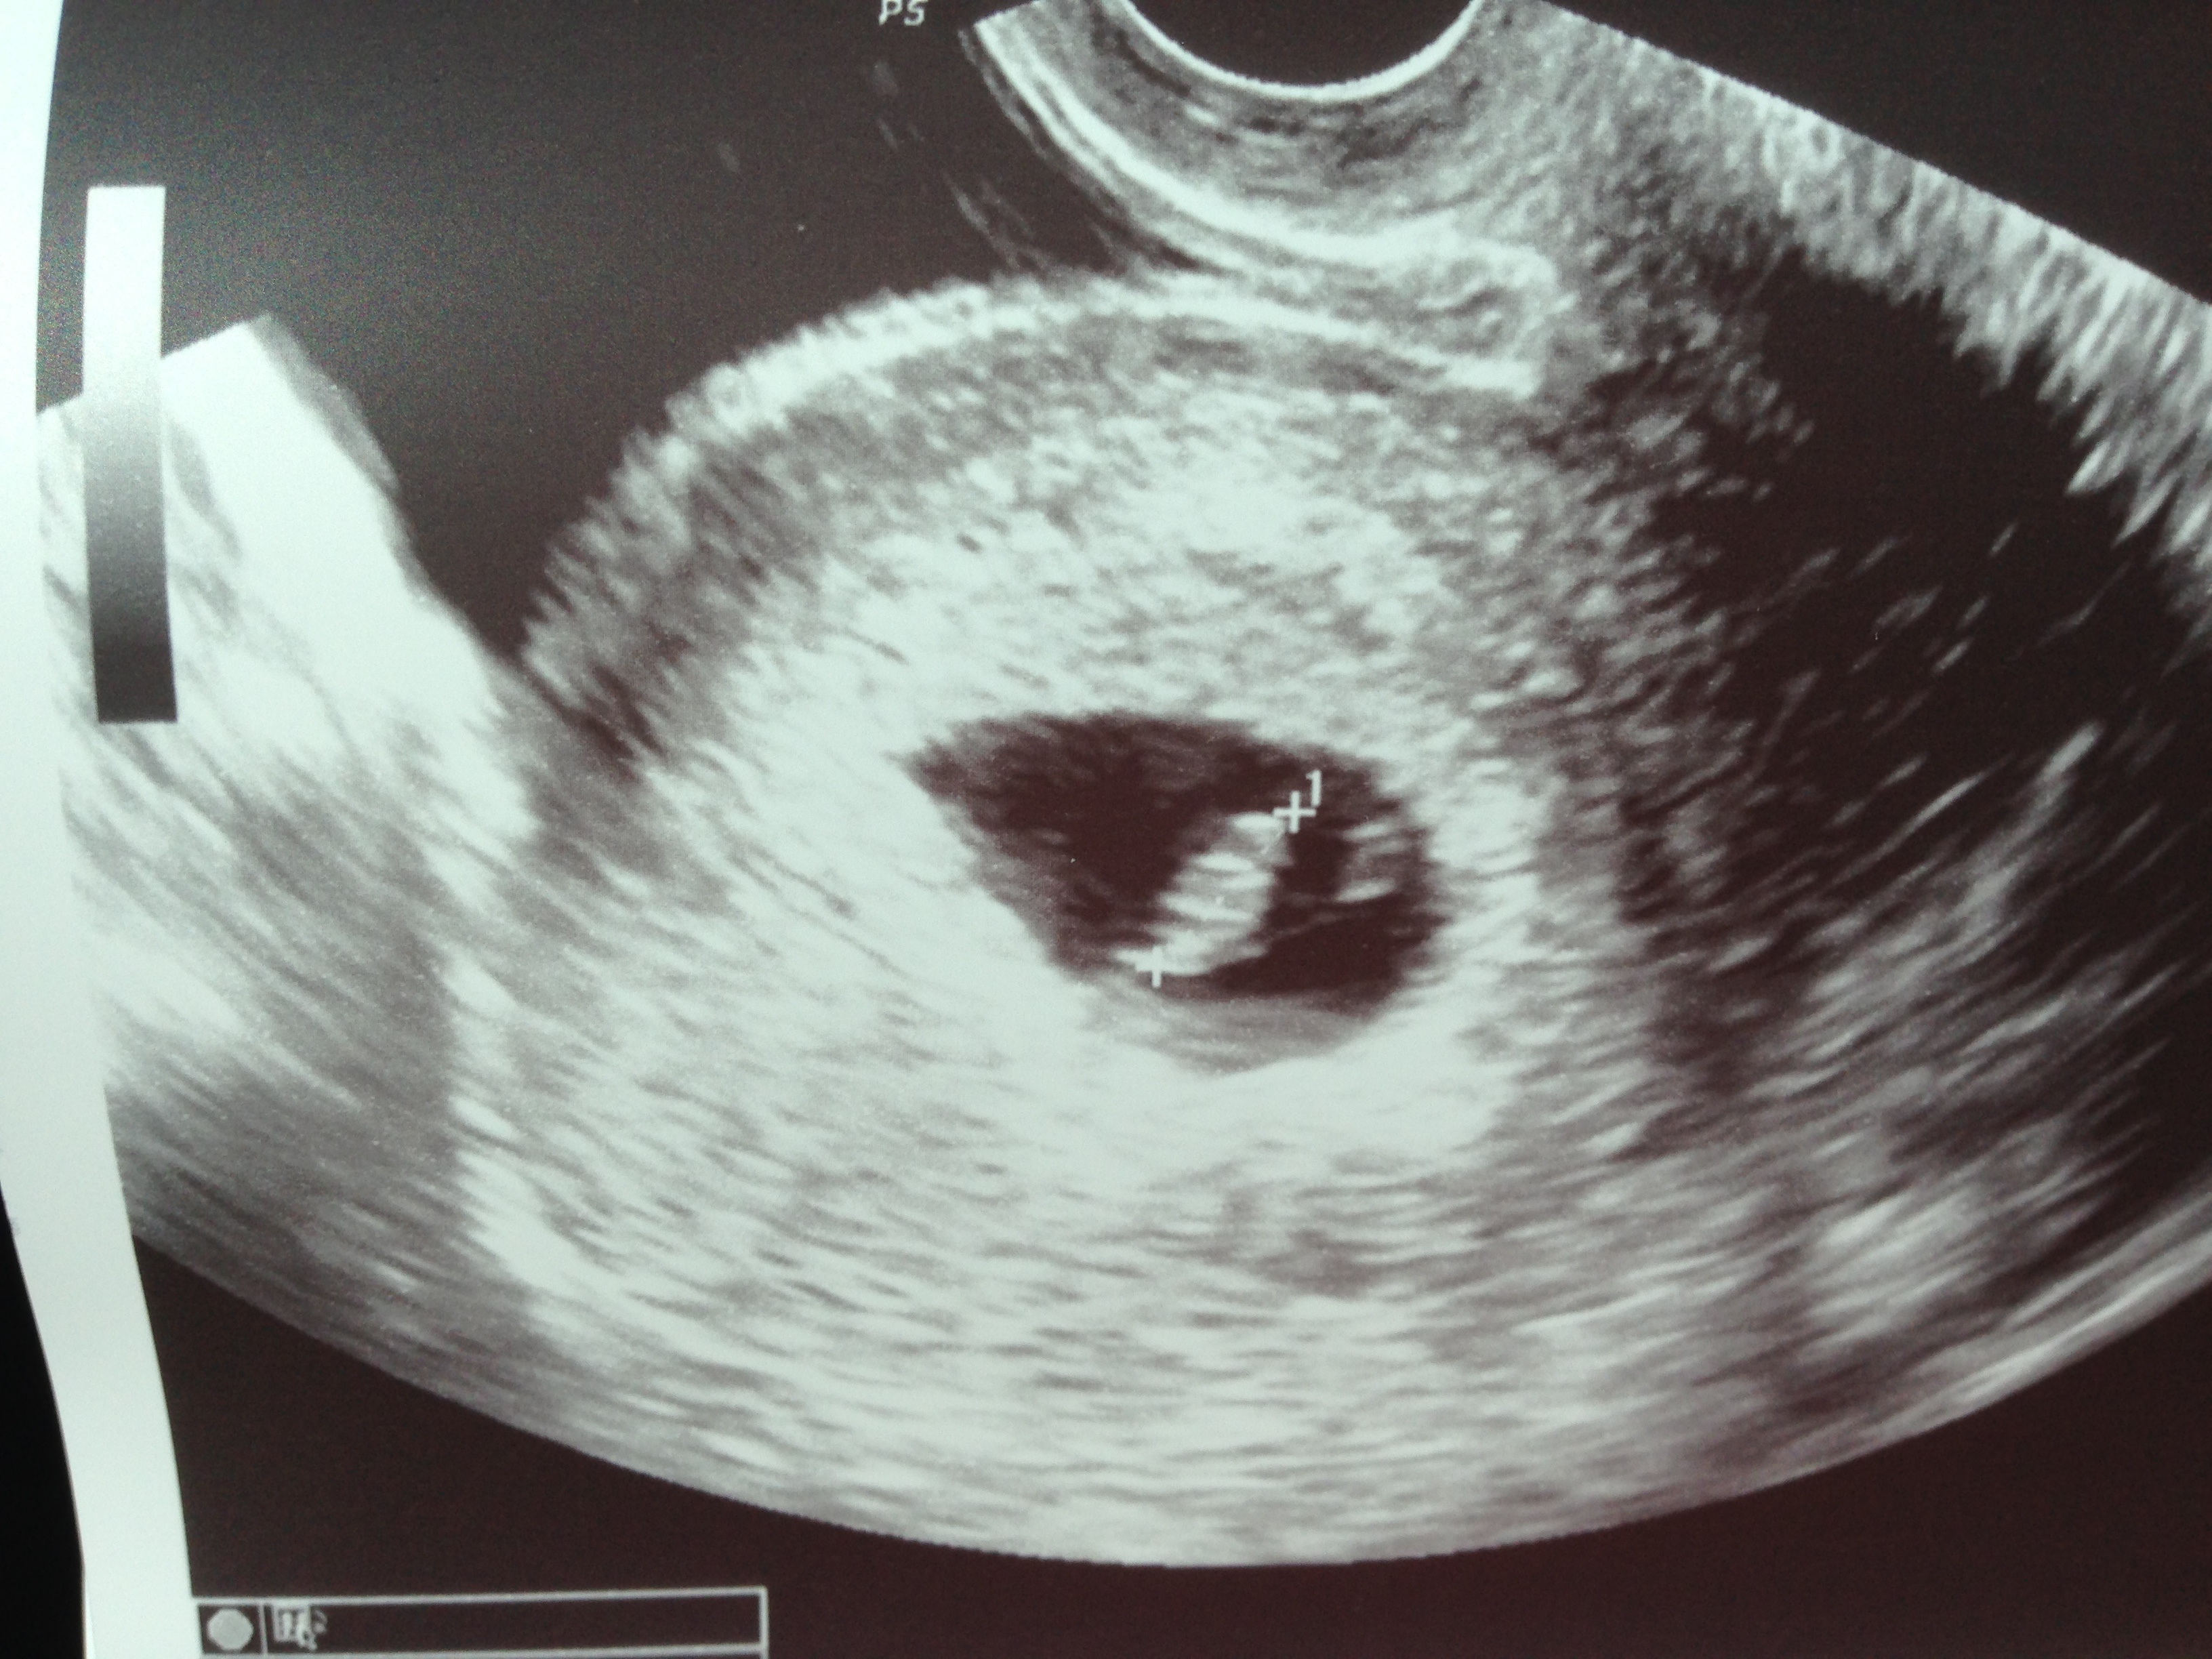

And this PgAler has been balling her eyes out since the RE started the ultrasound and said "you're really going to like this".

We have a healthy baby thriving with a heartbeat of 145bpm at 6w6d. Seeing that beautiful flicker...nothing better! My due date has been pushed up 2 days to 4/17/14 (2 days before DH's bday, which I love because I share my bday with my dad).

After 2 losses and no living children I am crying my eyes out with pure happiness, joy and excitement for this baby that I hope will be our rainbow.